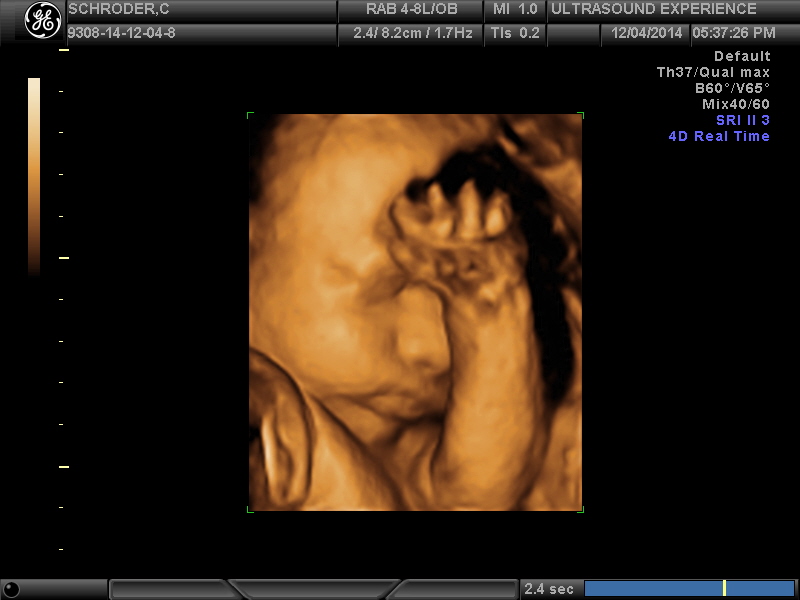

we saw you today

…and it was amazing. As if we couldn’t love you anymore…we do. Seeing your precious face in 4D was an incredible experience. We saw your facial features and they are so defined! You already have expressions that resemble mine and your dads and it was so awesome to see that 🙂 You are unbelievably adorable with a full head of hair, pronounced nose and mouth and scrumptious cheeks. You were very active during the ultrasound and were wiggling around and moving your tiny hands and feet non-stop. You smiled for us and even threw up a peace sign…just like your mama 🙂

It makes waiting another 9 weeks (give or take) even harder because we just want to meet you now!

All the grandparents joined us at the 4D & they are so in love with you also. We went out after to celebrate at an amazing sushi & robata japanese restaurant and you may have tasted the way too spicy shishito pepper I ate, sorry baby 😦